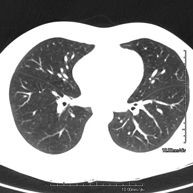

Prueba diagnóstica que consiste en obtener imágenes del tórax de alta definición anatómica (pulmones, corazón, mediastino, grandes vasos, caja torácica, etc.) mediante el empleo de un equipo de TC (Tomografía Computarizada). Dichas imágenes se estudian posteriormente en una estación de trabajo que permite reconstrucciones bidimendionales en diferentes planos del espacio y también reconstrucciones 3D (volumétricas). Algunos estudios requieren el empleo de contraste yodado para mejorar la definición de las imágenes. - Angio-TC Aorta torácica

Prova diagnòstica que consisteix en l'estudi del pulmó mitjançant l'ús d'un equip de TC (Tomografia Computeritzada) per obtenir imatges bi i tridimensional que permeten un estudi anatòmic altament específic del pulmó per poder valorar les estructures anatòmiques de petites dimensions. És una tècnica molt important en l'estudi dels pacients amb sospita de malaltia pulmonar. - TC d'estern